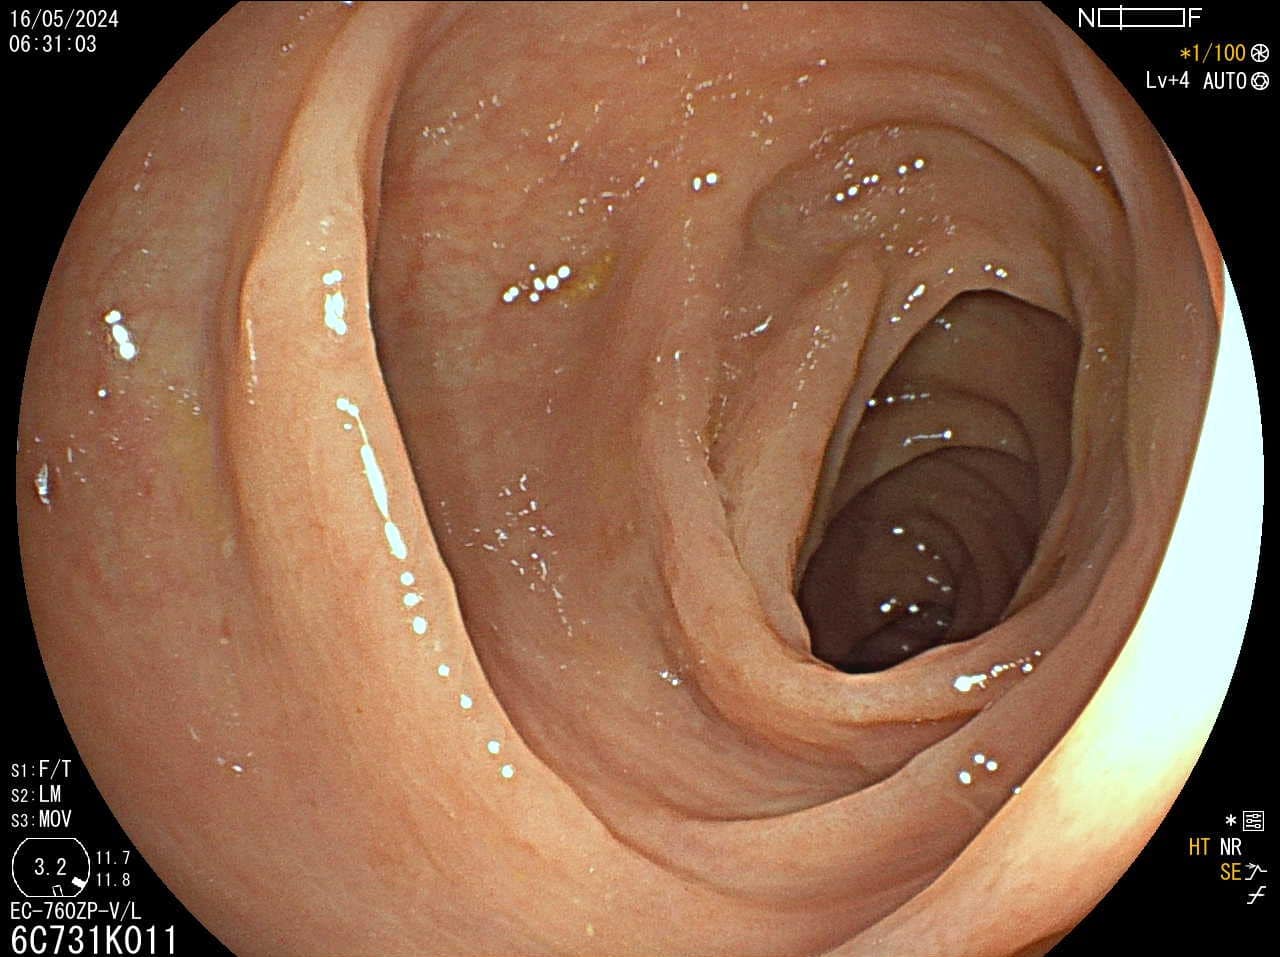

Pregled debelog crijeva

Kako bi pregled debelog crijeva bio temeljit potrebna je dobra priprema crijeva (očišćenost), no mali i plitki polipi, unatoč optimalnim uvjetima pretrage mogu ostati nezamijećeni, a zbog anatomije crijeva i skriveni iza nabora.